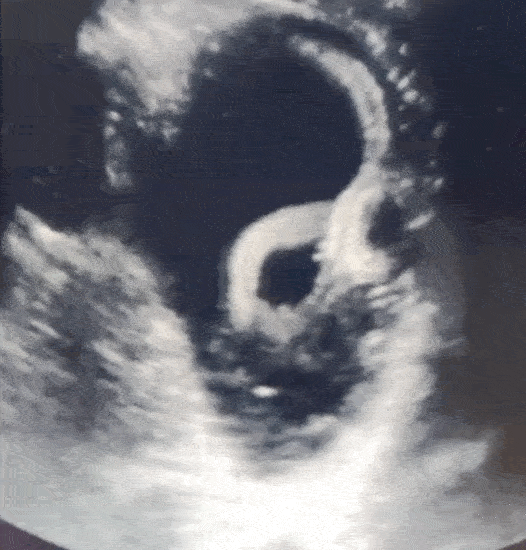

医生对患者的下腔静脉(靠近腹部的一条大静脉)进行了超声波扫描,以检查其血管中的血液水平。但在这一过程中,他们意外窥见他的胃内有一个管状结构并伴随着卷曲运动(见下面的动图)。